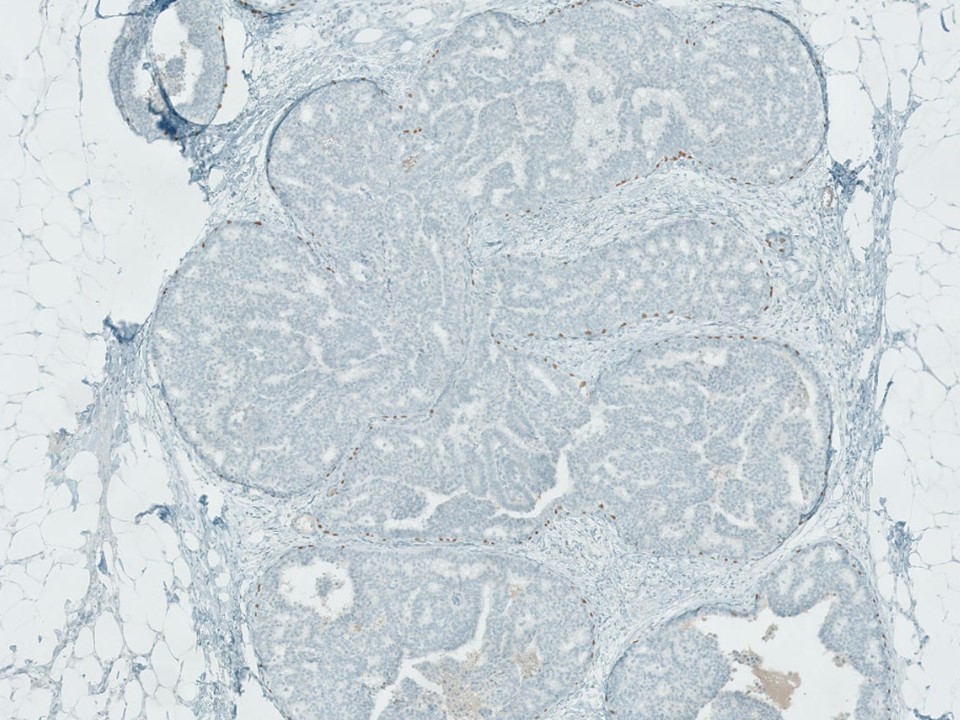

Complex Sclerosing Lesion, p63

Myoepithelial markers can help highlight myoepithelial cells within complex sclerosing lesions, although in some instances these markers can be lost.

See for reference: http://www.ncbi.nlm.nih.gov/pubmed/20463570